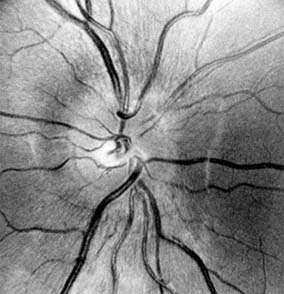

Figure 14-6

Figure 14-6: Examples of optic atrophy. Upper left: Primary optic atrophy due to nutritional amblyopia. Upper right: Secondary optic atrophy with retinochoroidal collaterals (arrows) due to optic nerve sheath meningioma. Lower left: Optic atrophy with optic disk drusen. Lower right: Pallor (atrophy) of right optic disk due to nerve compression by sphenoid meningioma. The left disk is normal.

Primary optic nerve sheath meningioma is a rare tumor most commonly presenting, like other types of meningioma, in middle-aged women (Figure 14-19). Five percent of cases are bilateral. Visual loss is slowly progressive. The classic clinical features are a pale, slightly swollen optic disk with retinochoroidal collaterals, but in most cases the collateral vessels are not present (Figure 14-6). Surgical excision invariably leads to complete loss of vision and is generally reserved for blind eyes to prevent intracranial spread of tumor. Focal radiotherapy is becoming more popular.

The usual clinical features of nutritional or toxic optic neuropathy are subacute, progressive, symmetrical visual loss, with central field defects (Figure 14-20), poor color vision, and the development of temporal disk pallor (Figure 14-6).

Adequate diet plus thiamine, folic acid, and vitamin B12 is nearly always effective in completely curing the disease if it is recognized early. Withdrawal of tobacco and alcohol is advisable and may hasten the cure, but innumerable cases are known in which adequate nutrition or vitamin B12 supplements effected the cure despite continued excessive intake of alcohol or tobacco. Improvement usually begins within 1-2 months, though in occasional cases significant improvement may not occur for a year. Visual function can but may not return to normal; permanent optic atrophy or at least temporal disk pallor can occur depending upon the stage of disease at the time treatment was started (Figure 14-6). Loss of the ganglion cells of the macula and destruction of myelinated fibers of the optic nerve-and sometimes of the chiasm as well-are the main histologic changes.